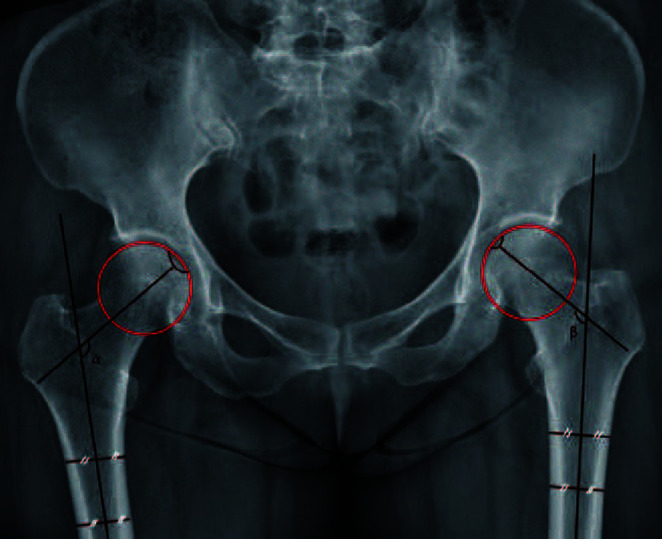

Purpose: Nondisplaced femoral neck fractures have traditionally been treated with in situ fixation. However, poor surgical and clinical outcomes have been reported for fractures with valgus deformity >15°, and the reduction of valgus impaction has recently been emphasized. In addition, early degenerative osteoarthritis can be caused by cam-type femoroacetabular impingement after healing of femoral neck fractures. This study was designed with the objective of confirming the difference in progression of radiographic osteoarthritis according to the severity of the valgus deformity.

Materials and methods: Patients who underwent internal fixation using multiple cannulateld screws for management of nondisplaced femoral neck fractures were divided into two groups: high valgus group (postoperative valgus angle ≥15°) and low valgus group (postoperative valgus angle <15°). Evaluation of demographic data and changes in the joint space width from the immediate postoperative period to the latest follow-up was performed.

Results: A significant decrease in joint space width in both hip joints was observed in the high valgus group when compared with the low valgus group, including cases with an initial valgus angle less than 15° and those corrected to less than 15° of valgus by reduction. No complications requiring surgical treatment were observed in either group; however, two cases of avascular necrosis, one in each group, which developed in the low valgus group after reduction of the fracture, were followed for observation.

Conclusion: Performing in situ fixation in cases involving a valgus deformity ≥15° in non-displaced femoral neck fractures may cause accelerated narrowing of the hip joint space.